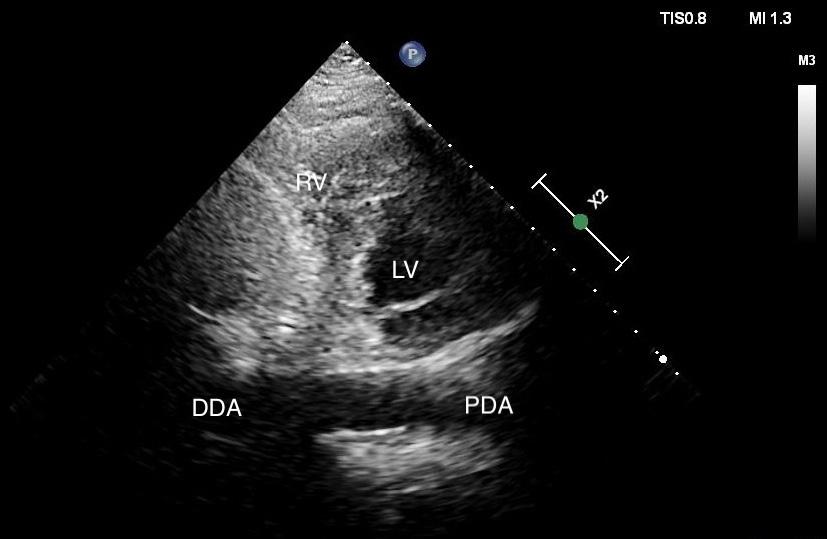

In the case covered in this article, an 85-year-old man with septic shock caused by a perforated sigmoid colon was profoundly hypovolemic and required crystalloid resuscitation and dual vasopressors. Ultrasound revealed that his internal jugular vessels were completely collapsible. Initial attempts to place the catheter were unsuccessful due to vessel collapse. The Trendelenburg position did not adequately dilate the internal jugular vein, as shown in Image 1. However, using a passive leg raise, significant dilation of the internal jugular vein was observed, enabling successful cannulation (Image 2).

Although the leg raise in this case was performed manually, using a hospital bed to elevate the legs could achieve similar results. This technique may prove useful in assisting with CVC placement in patients experiencing hypovolemic or vasodilatory shock with compressible vasculature. Further consideration and study of this approach may be warranted.